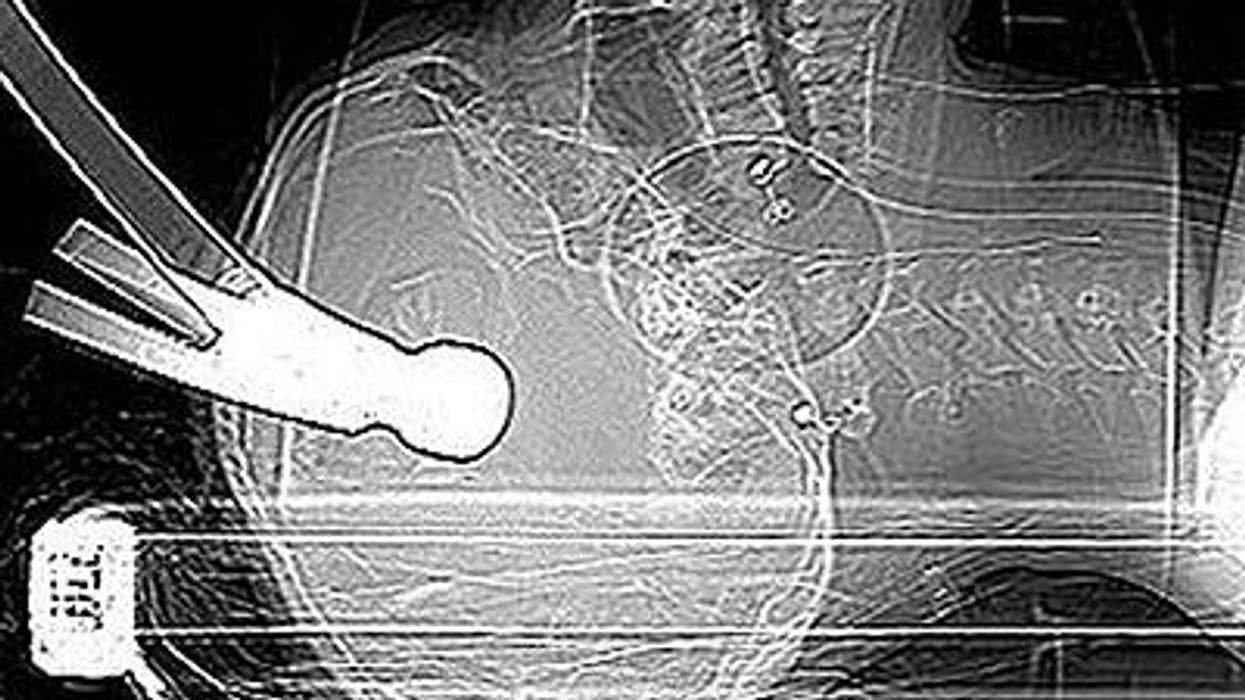

Prosecutors told the court that Kent Police found that Huntley was still alive, lying on an inflated airbed with a hammer embedded in his skull. Huntley and Williams had been matched as flatmates by their landlord. The night of the attempted murder was Huntley's first night in his new home.

"To hit someone more than once with a hammer in their sleep hard enough for the hammer to be embedded in their head clearly demonstrates an intention to kill them," prosecutor Philip Bennet told the court, according to the Standard.

Huntley suffered a depressed skull fracture and a penetrating brain injury, but miraculously survived the near-fatal injury, reports the Standard. His family has asked for privacy as Huntley recovers from brain damage caused by the attack.